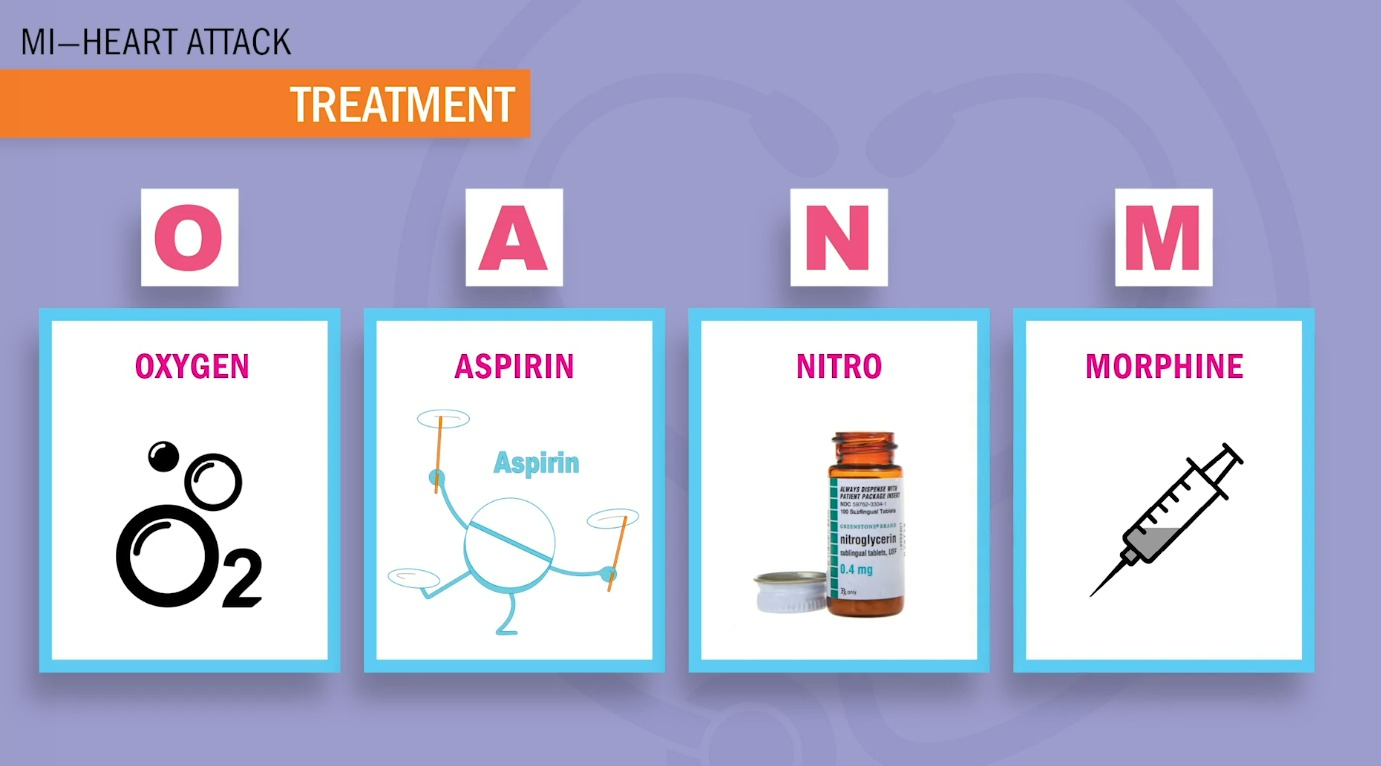

MI 중재(환자가 chest pain호소시 당장해줄수 있는것)

✔️O2

✔️Aspirin

✔️Nitro - ★주의사항 : 비아그라(-afil,Sildenafil절대금지 / 삼키지않고 혀밑에 녹이기 / 두통,혈압떨어지는건 예상된 반응 / 5분간격으로 3분까지만 복용하기 / 1번째 먹고 효과없으면 일단 구급차 부르고 2번째 약 먹기)

✔️Morphine : Morphine 투약 후 any chest pain = BAD! tissue death를 의미